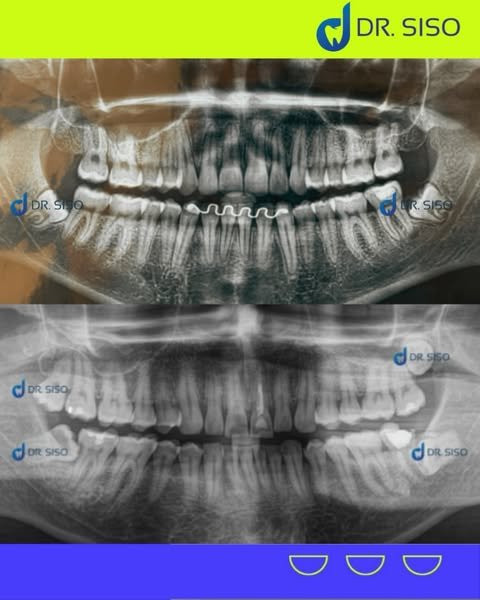

Aquele incômodo no fundo da boca pode ser causado pelos sisos! Quando não há espaço suficiente para nascerem corretamente, eles podem provocar dor, inchaço e até infecções. A extração do siso é um procedimento seguro que evita problemas futuros e alivia o desconforto.

Sim, em muitos casos. Mesmo sem dor, o siso pode estar mal posicionado, pressionando outros dentes, causando reabsorção óssea ou prejudicando a mordida. A avaliação clínica e radiográfica é essencial para decidir com segurança.

Sim! É comum extrair até os quatro sisos em um único procedimento, especialmente quando o paciente quer otimizar a recuperação e evitar múltiplas cirurgias.